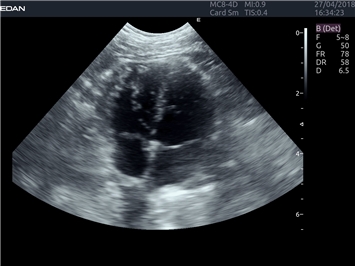

EDAN Acclarix LX4 VET

Расширьте свои представления. Когда речь заходит о стабильности, производительности и эффективности, существует одна ультразвуковая система, которая расширяет возможности ветеринарных исследований.

EDAN Acclarix LX4 VET представляет собой профессиональную ультразвуковую систему, специально разработанную для ветеринарных исследований. Сочетание стабильности, высокой производительности и эффективности делает эту систему идеальным выбором для современной ветеринарной практики.